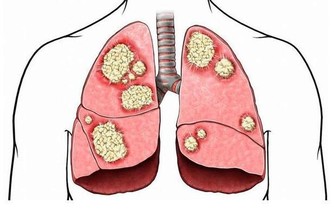

但是隨著年齡的增大,絕大多數的男人都會出現各種前列腺問題。50歲之前最可能出現的前列腺問題是前列腺炎,而50歲之後,男人的前列腺風險就成了前列腺增生和前列腺癌。